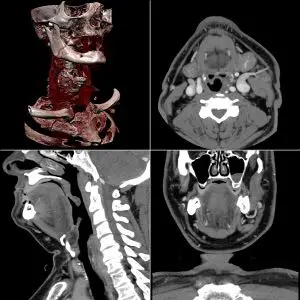

Abdominal and pelvic

CT is a sensitive method for diagnosis of abdominal diseases. It is used frequently to determine stage of cancer and to follow progress. It is also a useful test to investigate acute abdominal pain (especially of the lower quadrants, whereas ultrasound is the preferred first line investigation for right upper quadrant pain). Renal stones, appendicitis, pancreatitis, diverticulitis, abdominal aortic aneurysm, and bowel obstruction are conditions that are readily diagnosed and assessed with CT. CT is also the first line for detecting solid organ injury after trauma.

Oral and/or rectal contrast may be used depending on the indications for the scan. A dilute (2 percent w/v) suspension of barium sulfate is most commonly used. The concentrated barium sulfate preparations used for fluoroscopy e.g. barium enema are too dense and cause severe artifacts on CT. Iodinated contrast agents may be used if barium is contraindicated (for example, suspicion of bowel injury). Other agents may be required to optimize the imaging of specific organs, such as rectally administered gas (air or carbon dioxide) or fluid (water) for a colon study, or oral water for a stomach study.

CT has limited application in the evaluation of the pelvis. For the female pelvis in particular, ultrasound and MRI are the imaging modalities of choice. Nevertheless, it may be part of abdominal scanning (e.g. for tumors), and has uses in assessing fractures.

Multiplanar reconstruction

Multiplanar reconstruction (MPR) is the simplest method of reconstruction. A volume is built by stacking the axial slices. The software then cuts slices through the volume in a different plane (usually orthogonal). Optionally, a special projection method, such as maximum-intensity projection (MIP) or minimum-intensity projection (mIP), can be used to build the reconstructed slices.

MPR is frequently used for examining the spine. Axial images through the spine will only show one vertebral body at a time and cannot reliably show the intervertebral discs. By reformatting the volume, it becomes much easier to visualize the position of one vertebral body in relation to the others.

Modern software allows reconstruction in non-orthogonal (oblique) planes so that the optimal plane can be chosen to display an anatomical structure. This may be particularly useful for visualizing the structure of the bronchi as these do not lie orthogonal to the direction of the scan.

For vascular imaging, curved-plane reconstruction can be performed. This allows bends in a vessel to be 'straightened' so that the entire length can be visualized on one image, or a short series of images. Once a vessel has been 'straightened' in this way, quantitative measurements of length and cross sectional area can be made, so that surgery or interventional treatment can be planned.

MIP reconstructions enhance areas of high radiodensity, and so are useful for angiographic studies. mIP reconstructions tend to enhance air spaces so are useful for assessing lung structure.